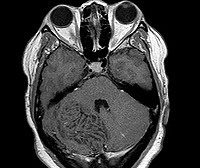

Диагностика болезни Лермитт-Дуклос производится посредством выявления характерных образований в мозжечке при помощи компьютерной и магнито-резонансной томографии. На КТ головного мозга при этом выявляется объемное гиперденсивное образование с размытыми и нечеткими краями, которое может быть расположено как на поверхности, так и в глубине мозжечка. МРТ головного мозга лучше всего производить с внутривенным контрастированием, поскольку именно такой метод позволит наилучшим образом изучить структуру и сосудистую сеть новообразования. При отсутствии технической возможности проведения данных исследований можно сделать рентгеновскую вентрикулографию - как правило, она показывает уменьшение или смещение четвертого желудочка и водопровода. Однако при незначительном размере ганглиоцитомы таких изменений может и не быть, поэтому вентрикулография не считается основным методом диагностики болезни Лермитт-Дуклос.